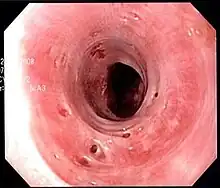

| Endoscopic image of esophageal intramural pseudodiverticulosis demonstrating the flask-like outpouchings of the esophageal wall. | |

Esophageal intramucosal pseudodiverticulosis (EIPD) is a rare condition wherein the wall of the esophagus develops numerous small outpouchings (pseudodiverticulae). Individuals with the condition typically develop difficulty swallowing. The outpouchings represent the ducts of submucosal glands of the esophagus. It typically affects individuals in their sixth and seventh decades of life. While it is associated with certain chronic conditions, particularly alcoholism, diabetes and gastroesophageal reflux disease, the cause of the condition is unknown. Treatment involves medications to treat concomitant conditions such as reflux (such as proton pump inhibitors) and esophageal spasm, and dilation of strictures in the esophagus.

The cause of esophageal intramucosal pseudodiverticulosis is uncertain. It has been hypothesized that the pseudodiverticulae are not a primary phenomenon, but rather are secondary to a chronic irritant to the esophagus, or to accentuation in the movement of the esophagus (hypermotility). Both of these factors lead to obstruction or compression of the submucosal ducts of the esophagus, leading to the formation of the pseudodiverticulae.[1] Autopsy specimens of individuals with esophageal intramucosal pseudodiverticulosis have confirmed that the flask-like openings are indeed dilated submucosal glands.[3] The condition is associated with alcohol use disorder, diabetes mellitus, and gastroesophageal reflux disease.[1]

Esophageal intramucosal pseudodiverticulosis is typically diagnosed at the time of endoscopy of the esophagus. Endoscopy shows evidence of the pseudodiverticulae, which are typically numerous, appear like pits in the wall, and may be preferentially located in the upper esophagus.[3][5] The mucosal lining of the esophagus may be inflamed, and this can be seen on endoscopy or on biopsy; the mucosa, however, may also be normal if esophagitis is not the cause of the pseudodiverticulosis. The condition must also be excluded from esophageal cancer, which may be done at the time of endoscopy, or which may require esophageal biopsy.[3]